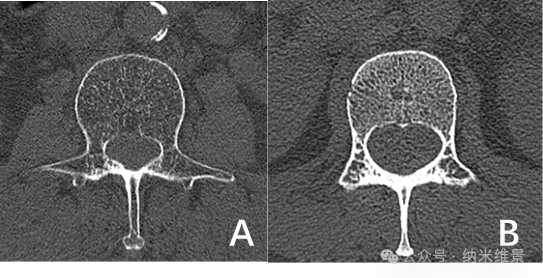

A.老年骨质疏松患者相控阵CT图 B.骨量正常的健康志愿者相控阵CT图

研究团队对100例受试者(老年组33例/中青年组67例)腰椎进行扫描,多项骨微结构指标变化显示:老年骨质疏松患者的骨小梁体积骨密度较中青年组显著下降,骨小梁连接密度有所减少。这种传统CT因分辨率不足难以清晰辨别的区域特异性差异,现可通过相控阵CT清晰呈现。